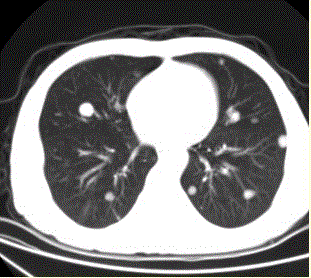

问题 患者男,45岁,因肝硬化、肝癌行肝移植术后6个月,咳嗽2周,来院复查。CR及CT影像如下图。 肺内转移结节可为

选项 A.弥漫性粟粒结节 B.单发结节 C.结节发生坏死形成空洞 D.钙化结节 E.带毛刺的结节 F.含脂肪成分的结节

答案 ABCDE

解析 ABCDE